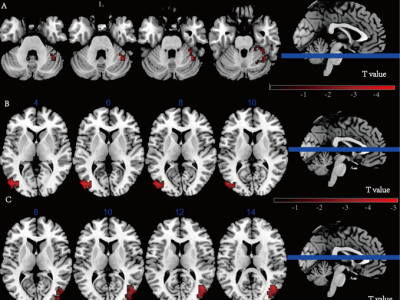

通知公告 教学培训 活动通知 | yl1111永利集团分析测试中心走进深圳理工大学——用户服务咨询会 04-05 通知公告 分析测试中心关于清明假期开放服务的通知 03-31 通知公告 活动邀请 | 2026年电镜样品制备技术交流会邀请函 03-27 通知公告 “职”为你来 | yl1111永利集团分析测试中心诚聘电镜实验技术人员 03-25 通知公告 服务上新 | 分析测试中心“跨校区(园)样品转运服务”上线! 03-25 通知公告 讲座报名 | 光镊悬浮单/双液滴精确拉曼测量方法技术及产业化前景 03-20 通知公告 分析测试中心实验技术人员培训之六十三 | X射线单晶衍射测试技术及应用案例分析 03-16 通知公告 >>more 应用培训(2026年度第4期)| 原位光电子能谱仪 ESCALAB QXi (东校园) 03-25 教学培训 应用培训(2026年度第3期)| Spectra Ultra 双球差校正透射电镜(南校园) 03-18 教学培训 应用培训报名(2026年度第1期)| 双球差电镜原位纳米力学样品杆培训(东校园) 01-12 教学培训 应用培训报名(2025年度第42期)| JEM-ARM300F2 双球差校正透射电镜(东校园) 11-25 教学培训 培训报名 | 冷冻电镜单颗粒数据处理培训(第1期) 11-10 教学培训 应用培训报名(2025年度第41期)| 基于高分辨液质联用仪的多组学应用培训(深圳校区) 10-22 教学培训 应用培训报名(2025年度第40期)| 微晶电子衍射(microED)应用培训(东校园) 10-16 教学培训 >>more 中心动态 党建工会 喜报 | 分析测试中心在2025年度高校实验室间比对活动中喜获佳绩 03-18 中心动态 刘承功书记带队开展春季学期初实验室安全飞行检查工作 03-18 中心动态 华中科技大学同仁到访分析测试中心调研交流 03-18 中心动态 分析测试中心召开教职工大会部署启动树立和践行正确政绩观学习教育 03-18 中心动态 yl1111永利集团分析测试中心加入港珠澳高校联合虚拟实验室 赋能湾区科创协同发展 01-27 中心动态 笃行实干 马踏新程:2025年,我们一起走过 01-22 中心动态 yl1111永利集团分析测试中心2025年度用户满意度及服务需求调研 12-30 中心动态 >>more 党建引领聚合力 共绘发展新蓝图——分析测试中心召开党员大会 03-20 党建工会 学前沿 强服务 共奋进 | 分析测试中心党支部与生物医学工程学院教工第三党支部、实验动物中心党支部开展主题党日活动 01-05 党建工会 筑牢大型仪器基石 担当分析测试新使命 | 分析测试中心主任吴丁财同志为中心党支部讲授专题党课 01-05 党建工会 坚持党建引领 落实三全育人 | 分析测试中心党支部第五党小组与地理科学与规划学院相关党支部联合开展主题党日活动 10-30 党建工会 精准测试助力科研突破 党建引领推进合作新篇 | 分析测试中心党支部与物理学院物理学系教工党支部联合主题党日活动顺利举办 10-13 党建工会 深化八项规定学习,凝聚强国复兴力量——分析测试中心党支部集中观看九三阅兵仪式扎实开展7-8月组织生活 09-20 党建工会 支部共建聚合力 同心共融促发展——分析测试中心党支部与深圳检测院轻化党支部开展党建联建活动 07-16 党建工会 >>more 仪器介绍 仪器试运行(南校园)| 双球差校正透射电镜(Spectra Ultra) 仪器试运行(东校园)| JEM-ARM300F2原位双球差校正透射电镜 仪器试运行(东校园)| 电感耦合等离子体光谱仪和同步热红外气质联用仪 高分辨冷场扫描电镜真空转移系统 冷冻超薄切片机(徕卡EM UC7+EM FC7) X射线显微镜(XRM/CT) 深圳校区分中心有新仪器上线啦~欢迎师生们前来使用 深圳校区分中心仪器设备上新啦~(内含福利) >>more 仪器支撑成果 声光齐驱,效率倍增!分析测试中心助力我校刘军民/周业成团队研发新型COF材料,实现水分解催化性能突破 分析测试中心助力我校松阳洲/刘峰团队系统绘制人类细胞核内无膜凝聚体邻近蛋白网络全景图 突破钠电池实用化瓶颈!分析测试中心助力我校雷丹妮/王成新团队创新梯度双层负极,能量密度超200 Wh kg⁻¹ 分析测试中心助力我校张溢/郑跃团队在极性微结构及其动力学方向取得系列成果 分析测试中心助力我校孟凡刚/赵姗姗团队在高性能纳滤膜研究领域取得新进展 分析测试中心助力中山一院王楚怀团队探究间歇性θ节律刺激对慢性腰痛患者疼痛缓解的效果及其潜在机制 分析测试中心助力我校张潇悦/郑跃团队在极性与分子构象耦合关系的纳米尺度表征新方法上取得进展 锦旗映初心 服务显担当 | 分析测试中心助力世界首款PB2靶点抗流感一类创新药获批上市 更多 text here yl1111永利集团大型科研仪器开放共享平台 实验室信息管理系统-仅保留校内用户结算功能 分析测试中心校内送样须知 实验室仪器 广州校区南校园分中心 广州校区东校园分中心 深圳校区分中心 珠海校区分中心